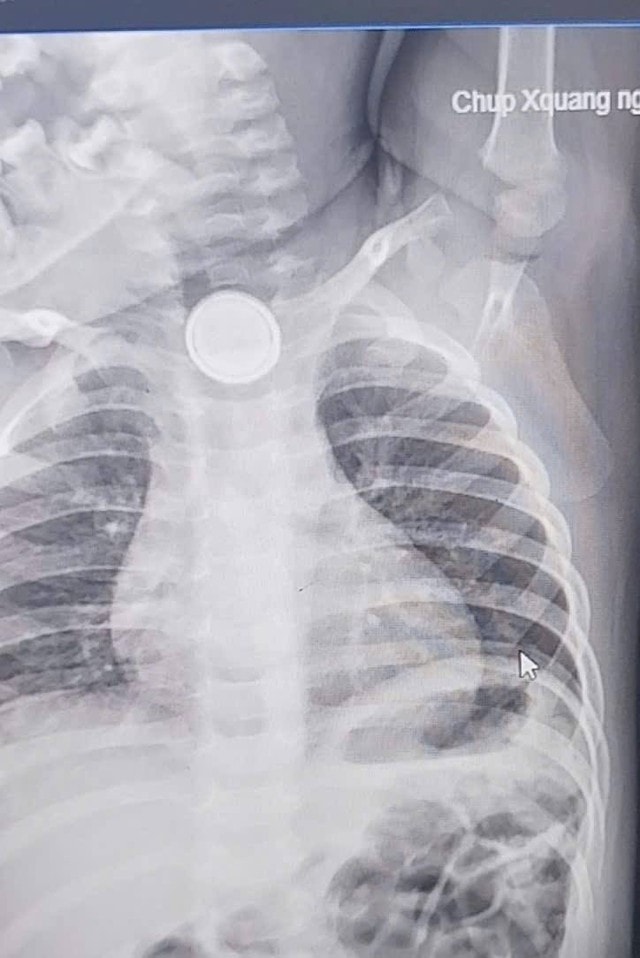

Ngày 1/4, thông tin từ Khoa Tai Mũi Họng (Bệnh viện Sản Nhi Nghệ An) cho biết, đơn vị vừa tiếp nhận và xử trí một trường hợp bệnh nhi 24 tháng tuổi nuốt phải pin cúc áo.

Qua thăm khám và chụp chiếu, các bác sĩ xác định dị vật mắc tại thực quản. Do lưu giữ nhiều ngày, niêm mạc thực quản đã bị bỏng nặng. Ngay sau đó, bệnh nhi được chỉ định nội soi gắp dị vật và hiện đang được theo dõi sát do nguy cơ biến chứng.